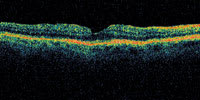

| Figure 3. This patient has vision of 20/30, but has an early apparent peeling of the inner retina along one side of the fovea. This may represent a laterally ruptured cyst and may or may not represent an early macular hole formation. |

A central clinical challenge has been accurately diagnosing early macular holes which may be mimicked by many other conditions.34,35 No imaging modality has enhanced our diagnostic capability more than the OCT; superior imaging capabilities have improved diagnostic accuracy, clinical monitoring, and postoperative assessment.36-38 The OCT unequivocally demonstrates early stages of full-thickness macular holes (Figure 1), and allows distinction of pseudohole and pre-macular hole conditions in almost all instances. Fluid accumulation in early, presumed pre-macular hole stages have been corroborated by OCT observations (Figure 2). Serial images have been reported showing the progression from apparent impending macular holes to full thickness macular holes.39-42 It has depicted many other configurations that might be in the spectrum of lamellar or pre-macular hole conditions (Figure 3 and 4).